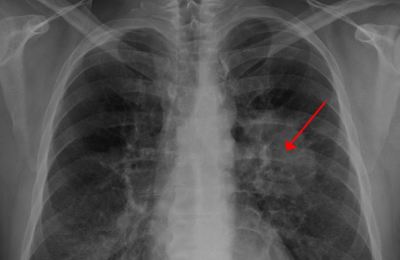

가장 일반적으로 시행되는 검사는 흉부 X선 촬영과 CT 스캔입니다. 이러한 검사를 통해 폐에 이상 징후가 있는지를 확인할 수 있습니다. 초기 증상이 나타나는 경우 때에 따라 추가 검사가 필요할 수도 있습니다.